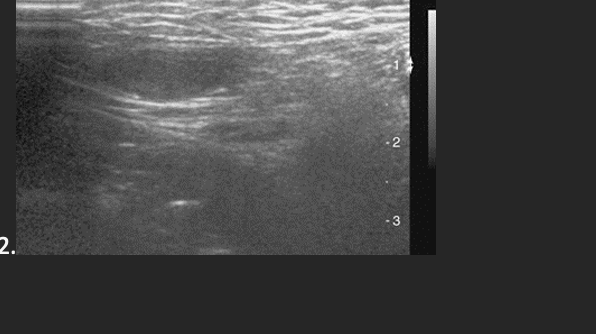

A 35 year old patient presents with a palpable scrotal mall. He is afebrile and denies any scrotal pain. This is most suspicious for what abnormality?

B. Testicular Torsion